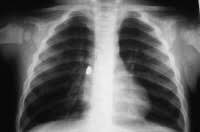

Ağlasığmaz hadisə: uşağın ağciyərindən görün nə çıxarıldı - VİDEO